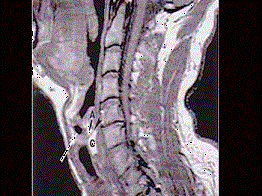

问题 男,16岁,咽异物感6年,无咽部出血及吞咽障碍。检查:舌根部中央有半球形肿物隆起,粘膜光滑,质地中等。颈部淋巴结不大: MRI检查结果如下图,下一步最重要的检查是 ( )

选项 A、针吸活检 B、纤维喉镜 C、颈部CT D、放射性I扫描 E、颈部彩超

答案 D

解析 D